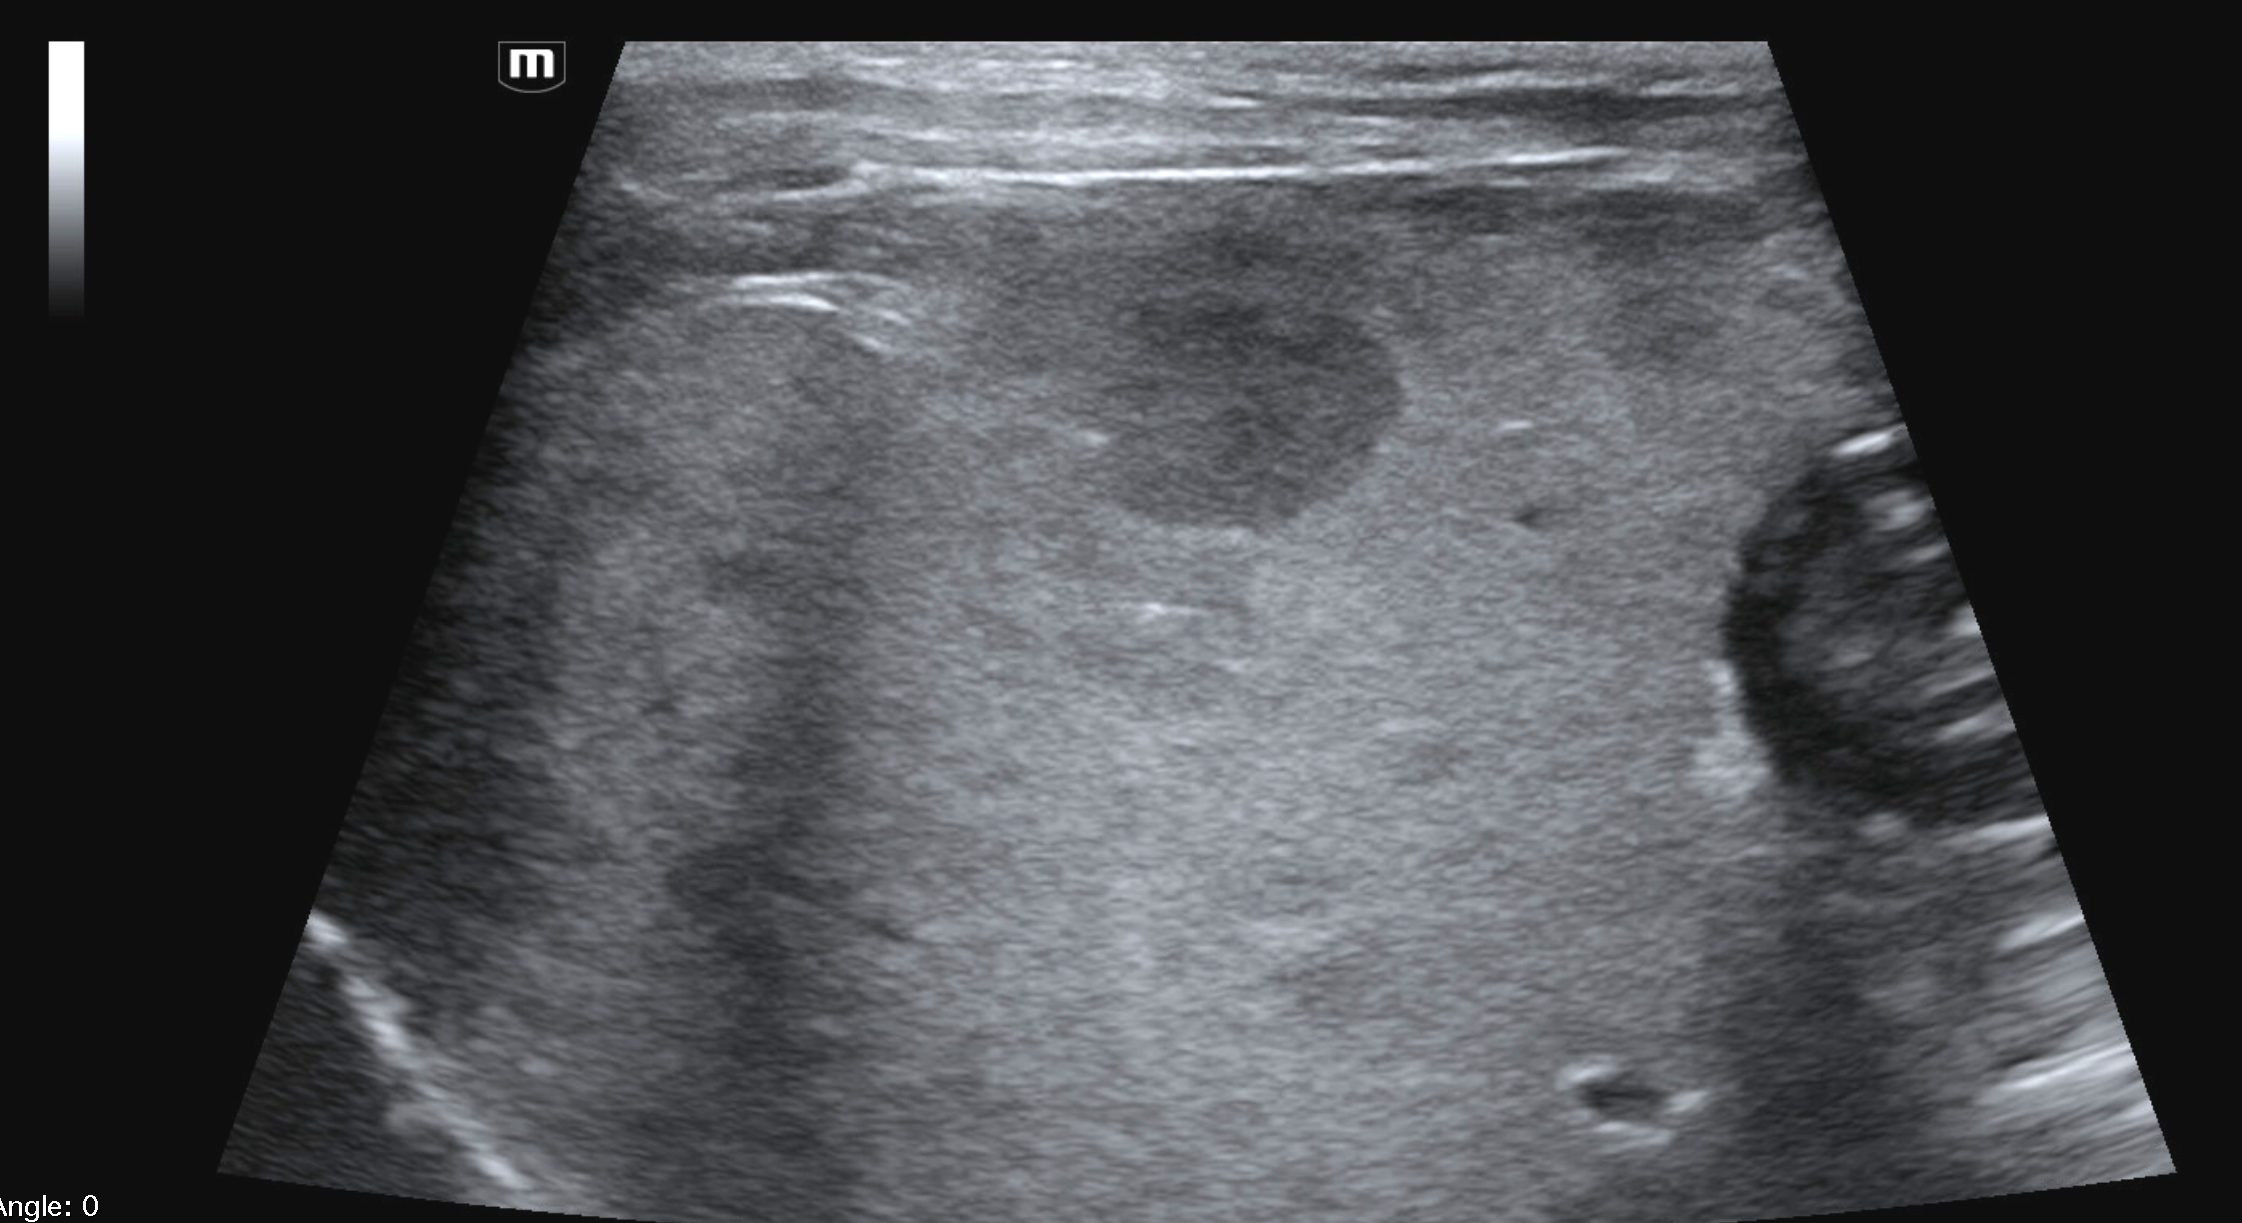

Which of these liver masses/nodules is a malignant tumor.

Focal liver lesions are a common ultrasonographic finding in dogs, particularly in middle-aged to older patients. These lesions encompass a wide spectrum of pathological processes, including benign hyperplastic nodules, primary hepatic neoplasia, and metastatic disease. Ultrasonography is the first-line imaging modality for hepatic assessment due to its availability, lack of ionizing radiation, and ability to guide sampling. However, despite continual advances in ultrasound technology, imaging characteristics alone are frequently insufficient to differentiate benign from malignant liver masses, making cytologic or histopathologic sampling essential in the majority of cases.

B-mode ultrasonography is highly sensitive for detecting focal liver lesions but is poorly specific for lesion type. Hepatic masses may appear:

• Hypoechoic, hyperechoic, or mixed echogenicity

• Well-marginated or irregular

• Solitary or multifocal

Importantly, echogenicity does not correlate reliably with malignancy. Multiple studies have demonstrated substantial overlap in the sonographic appearance of benign nodules, primary hepatic tumors, and metastatic lesions (Nyland et al., 2002; O’Brien et al., 2004)

In a large retrospective study of canine liver tumors, no consistent B-mode ultrasonographic features reliably differentiated hepatocellular carcinoma, cholangiocarcinoma, sarcoma, or metastatic lesions, aside from lesion distribution (O’Brien et al., 2004). Hepatocellular carcinomas were more likely to be solitary, whereas sarcomas and metastases were more often multifocal, but significant overlap existed.